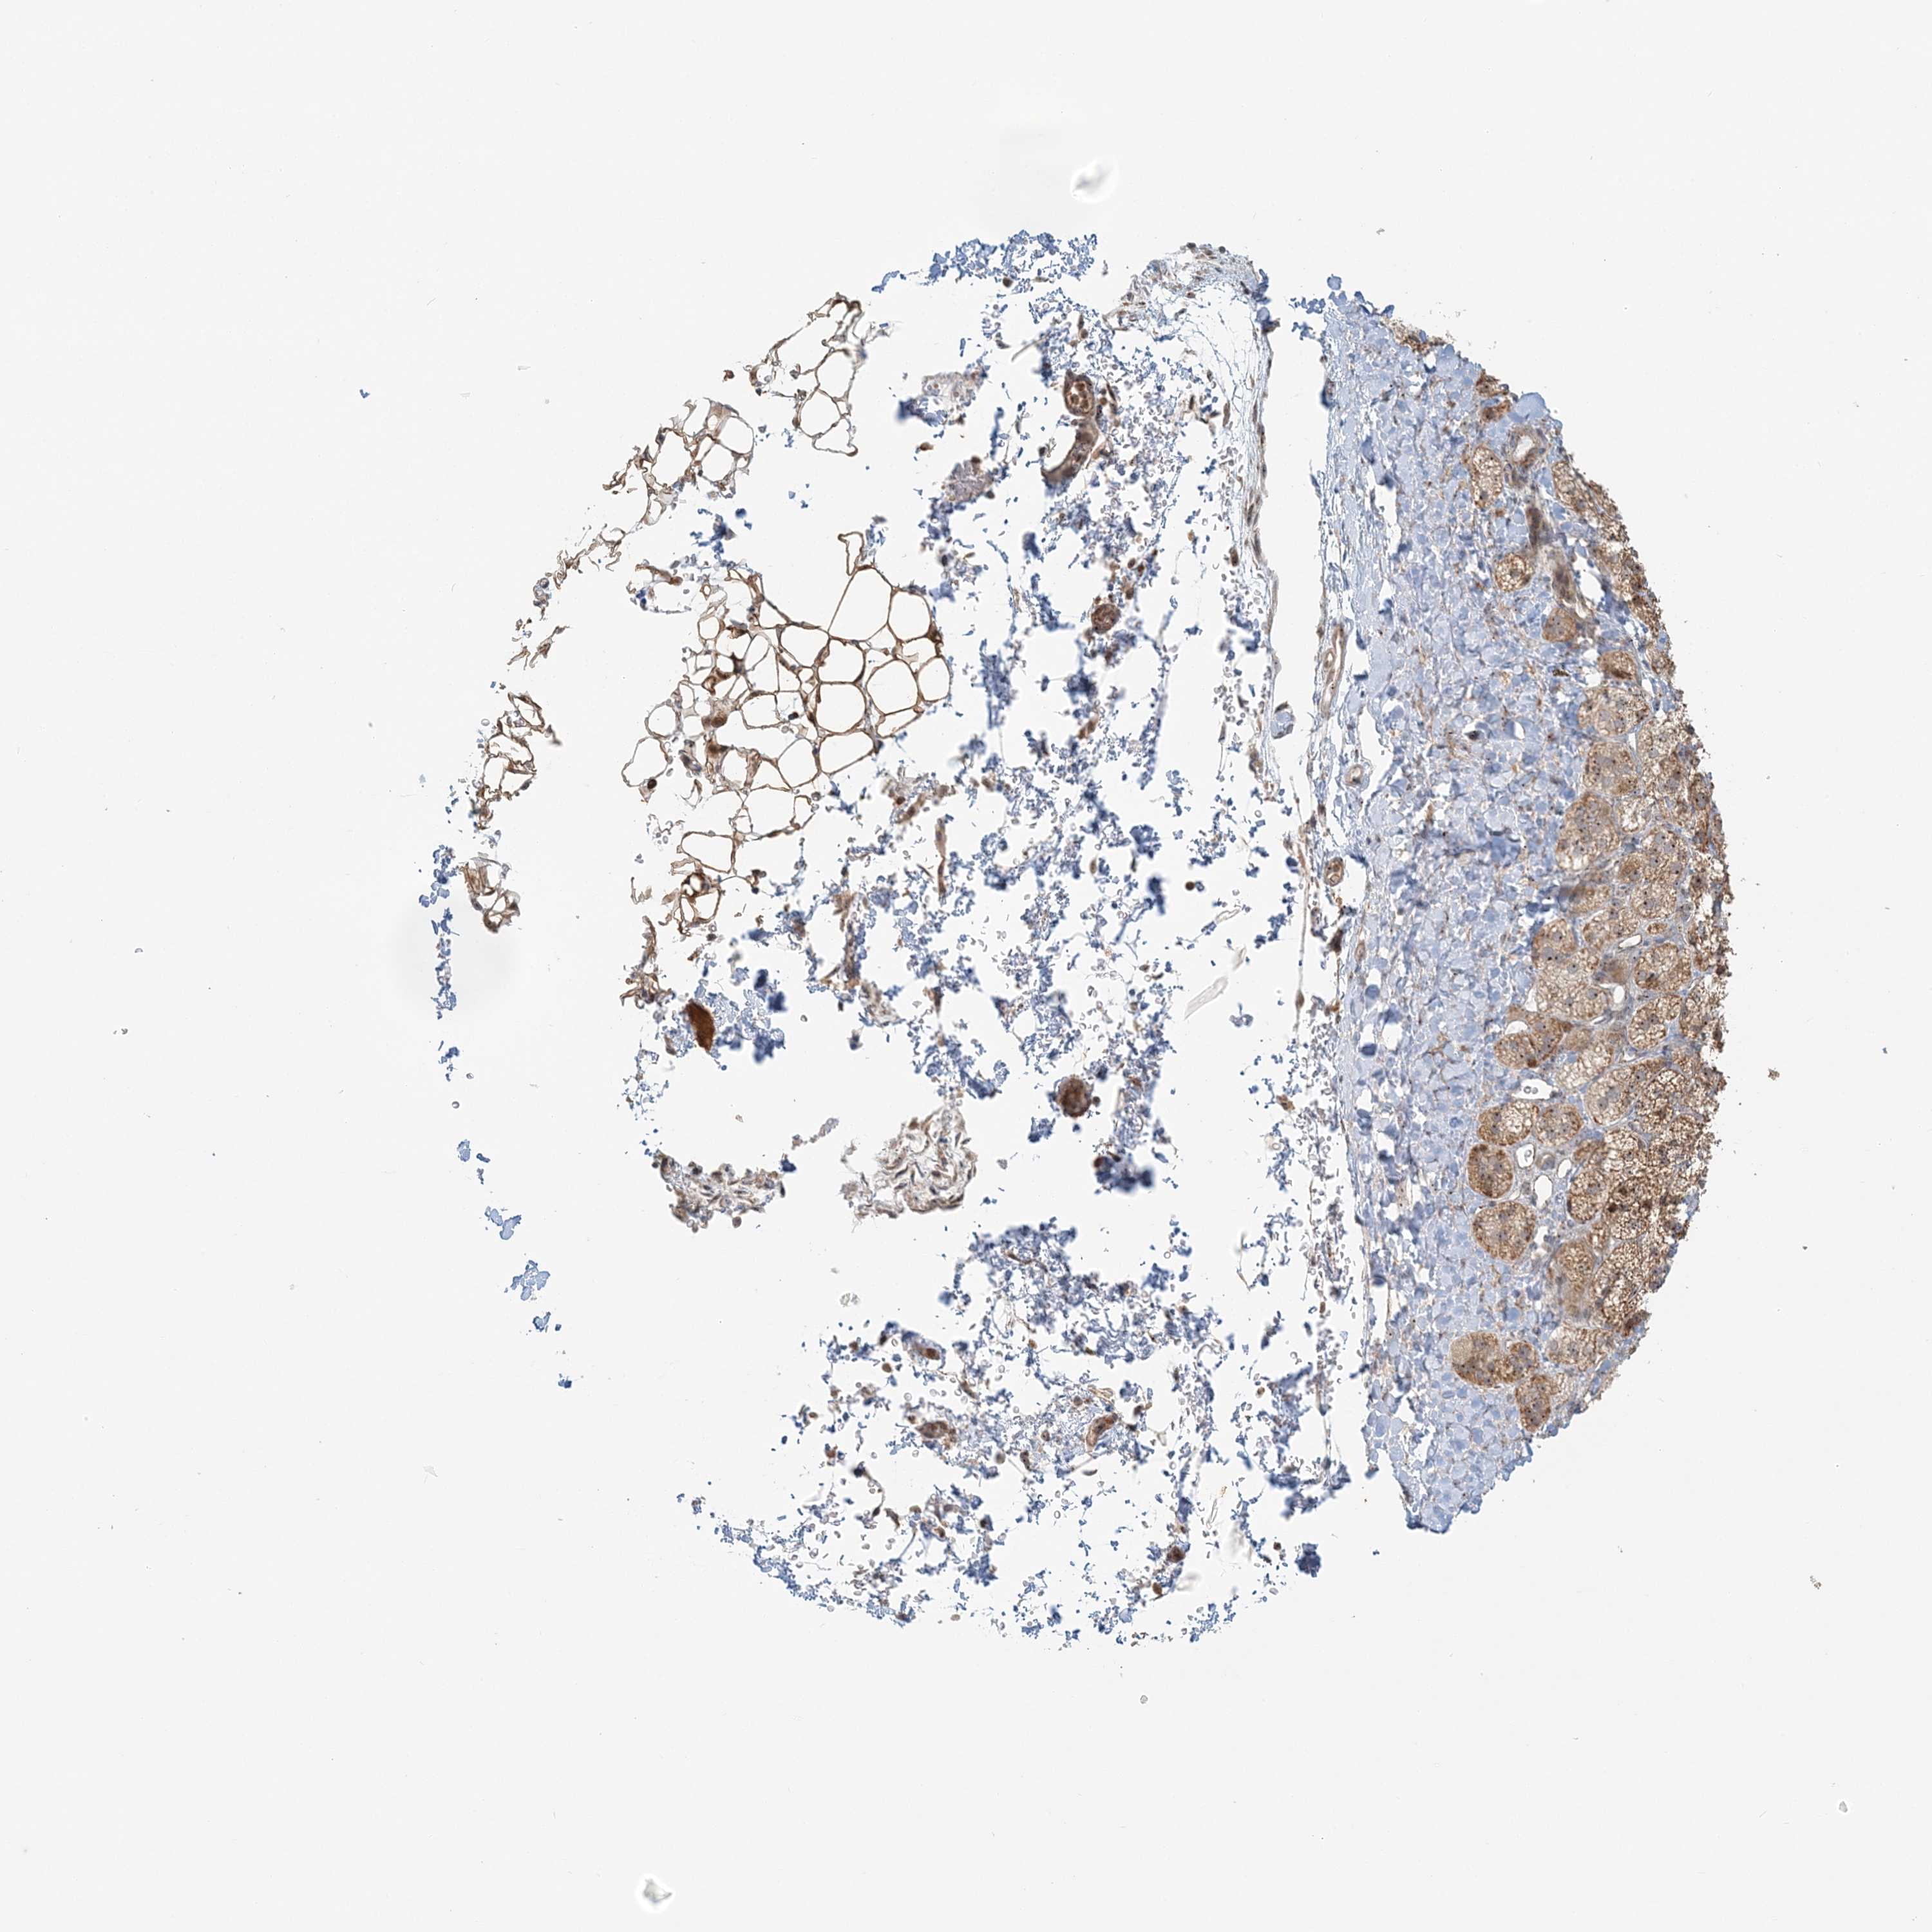

ADRENAL GLAND - Antibody stainingi

Antibody staining in the annotated cell types in the current human tissue is reported as not detected, low, medium, or high, based on conventional immunohistochemistry profiling in selected tissues. This score is based on the combination of the staining intensity and fraction of stained cells.

Each image is clickable and will lead to virtual microscopy that enables deeper exploration of all samples and also displays staining intensity scores, fraction scores and subcellular localization as well as patient and tissue information for each sample.

Antibody HPA037444

Glandular cells Medium